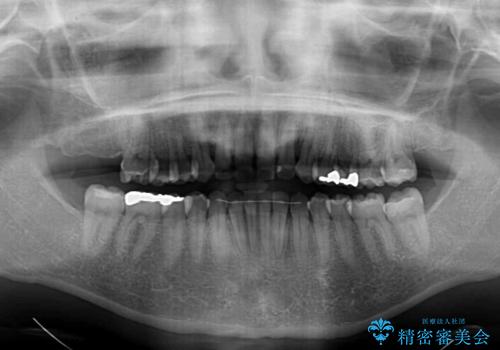

- 前歯のデコボコを気にして来院された患者様です。

主に下顎歯列全体の後方移動とIPR(歯と歯の間を削る)によってデコボコが解消するように設計し、インビザラインにより治療を行うこととしました。

舌突出癖がある方ですと、叢生が解消すると同時に前方に拡大されてしまいますが、ゴムかけをしっかりと行ってくださったこともあり、スッキリとした仕上がりとなりました。